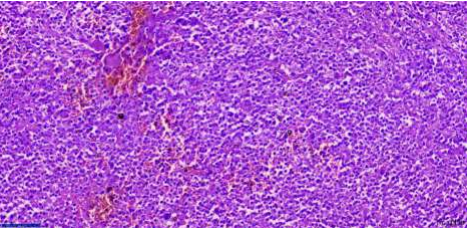

Post-surgery histopathology report was suggestive of non-Hodgkin’s lymphoma. Microscopic examination showed large atypical lymphoid cells with scant cytoplasm and vesicular nuclei with distant nucleoli, classical of diffuse large B cell lymphoma (DLBCL) (Fig. 3). Immunohistochemistry (IHC) was done to confirm and further type and grade the lymphoma. IHC findings were diffuse reactivity for CD20 (pan B cell antigen) with high Ki67 proliferation index of 95% (Fig. 4a and b); also dim nuclear reactivity for transcription factor Multiple Myeloma 1(MUM1), suggestive of DLBCL non-germinal centre type (Fig. 4c).

Fig. 3. High power histopatological images showing monotonous infiltrate of large atypical lymphoid cells with scant cytoplasm and vesicular nuclei suggestive DLBCL.